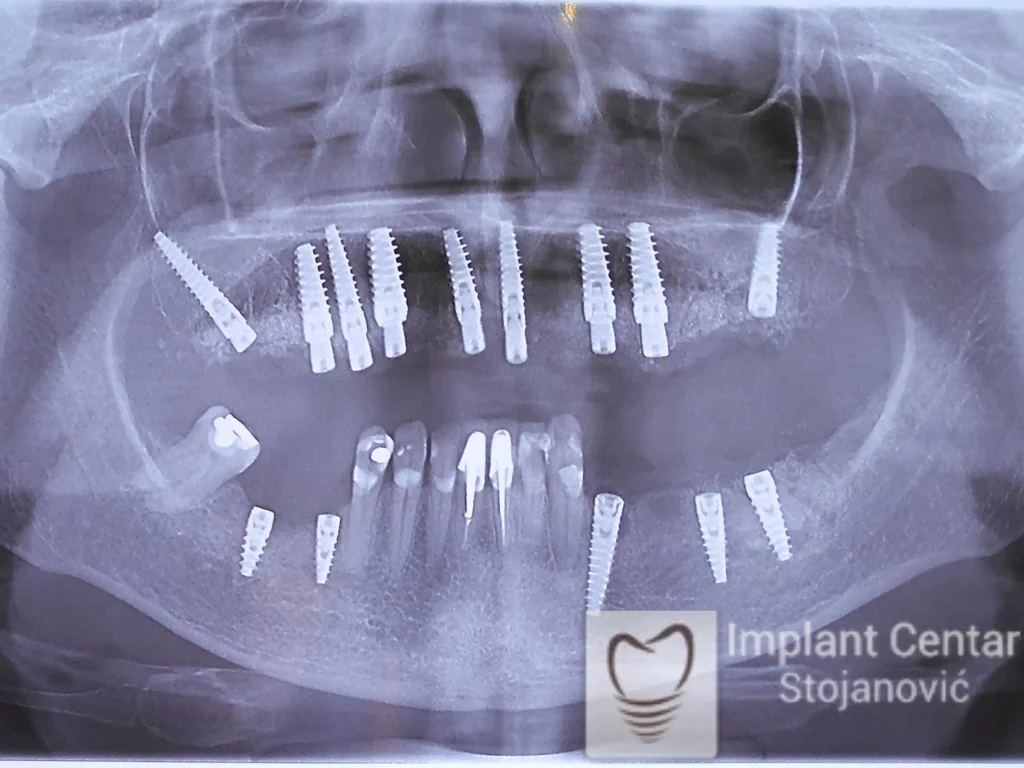

Na slici 1. i slici 2. prikazan je izgled pacijenta pre početka terapije – klinički i rendgenološki.

Nakon vađenja zuba, ugrađeni su implantati. Na slici 3 prikazan je ortopan snimak sa ugrđenim implantatima. Tokom perioda osteointegracije, pacijent je bio zbrinut fiksnim privremenim krunicama na implantatima, koje su izrađene samo dva dana nakon hirurške intervencije.